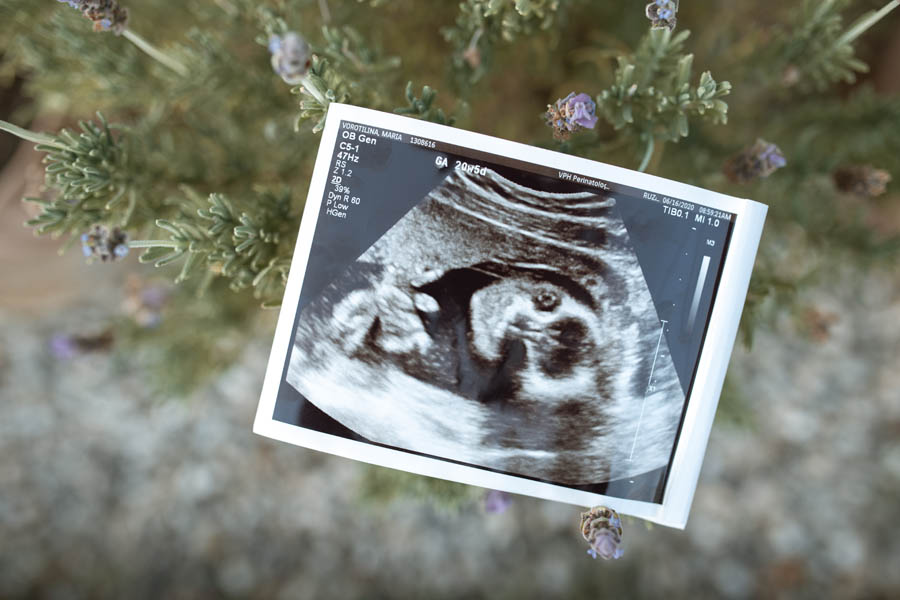

Underneath the picture of the seven-week amniotic sac, the article says, “Above is pregnancy tissue at seven weeks. There is still no visible embryo.” There’s just one problem: an embryo at seven weeks is very much visible. Sources as diverse as WhatToExpect.com (reviewed by medical experts), Mayo Clinic, and the British National Health Service (among countless others) offer data on fetal development; they all agree that, at seven weeks, a baby is between .3 and .5 inches long—about the size of a pomegranate seed. That’s small, to be sure, but it’s certainly visible to the naked eye. In fact, many expectant parents get their first look at their baby around week 8, when an ultrasound reveals an actual-size tiny person with a clear, strong heartbeat.

From this point, the article’s misleading claims become only more egregious. The article relies on the words of Dr. Joan Fleischman, who describes herself as a family doctor. Dr. Fleischman insists that, through week nine, “there is no visible embryo.” Beneath a photo claiming to be “everything that would be removed during an abortion” at nine weeks, the article asserts that, at this point, the “embryo… is not easily discernible to the naked eye.” But at nine weeks, the baby is nearly three-quarters of an inch long—in other words, nearly the size of a paper clip, a green grape, or an AirPod Pro earbud. Those things are all “easily discernible to the naked eye,” so why not an embryo? Nine-week ultrasounds show a tiny person with a discernable head, body, and buds of arms and legs.

The unavoidable conclusion here is that The Guardian simply decided that it didn’t want its readers seeing a nine-week-old embryo—possibly because they know the statistic that around 80% of abortion-minded women who see their baby in an ultrasound choose life. We cannot say with certainty why The Guardian’s pictures show only amniotic tissue and no embryo. We cannot know if the embryos were deliberately removed or strategically covered up. But we do know that the photos are misleading. The writers misuse these photos to imply that early pregnancy is merely a woman’s body preparing for a baby by making cottony tissue, when, in reality, early pregnancy is a vibrant time of actual human development. They make early pregnancy seem like making an empty bed, when really it is more like tucking a child in for a good night’s sleep.

Many women who have experienced miscarriages before their 10th week of pregnancy responded to The Guardian’s story with anger and frustration. Some shared heart-breaking photographs (caution, graphic content) of their own miscarried babies from weeks eight, nine, or 10—photographs that show delicate faces, eyes, tiny noses, and distinct arms and legs (and fingers!) on bodies that are very easily discernible to the naked eye.